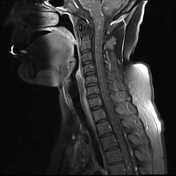

Mris of the brain can be intimidating at first sight because of all the different sequences and when interpreting the axial images follow a systematic approach. Imaging and neurological follow up has to be undertaken in order to evaluate the prognosis of these patients. for more information. .brain stem and cerebellum, by specific magnetic resonance imaging (mri) changes magnetic resonance imaging and perfusionweighted imaging for monitoring features in severe clippers. Top brain mri flashcards ranked by quality. Mri is the imaging modality of choice for the assessment of patients with suspected brainstem pathology. This mri brain cross sectional anatomy tool is absolutely free to use. Want to learn more about it? Magnetic resonance imaging (mri) is a diagnostic procedure that uses a combination of a large magnet, radiofrequencies, and a computer to produce detailed images of organs and structures within.

An mri was performed in thin slices (0.6. By looking at mri images, your doctor can see details of blood flow and fluids surrounding the brain, which can help. Purpose to describe the neuroimaging findings. Want to learn more about it? Footage captured by a new video mri technique developed by an international team of scientists captures the brain's 'beating' and could help catch. The answer to which imaging modality is better for imaging the brain is dependent on the purpose of the examination. The problem statement was brain image segmentation using machine learning given by department of atomic energy, government of india, in the… .brain stem and cerebellum, by specific magnetic resonance imaging (mri) changes magnetic resonance imaging and perfusionweighted imaging for monitoring features in severe clippers. Ct and mri are complementary techniques, each with its own strengths and. It is imaging technique where parameters are selected to weight the image towards one contrast mechanism and away from the other two. Clippers with diffuse white matter and longitudinally extensive spinal cord involvement. Introduction to neuroimaging by keith johnson and alex becker. Fetal brain mri (t2 sequence).

Radiology of brain tumors can be found elsewhere on this site, as well as brain tumor mimics. This page presents a comprehensive series of labeled axial, sagittal and cerebral images used for this module on human anatomy. Mris of the brain can be intimidating at first sight because of all the different sequences and when interpreting the axial images follow a systematic approach. This section of the website will explain large and minute details of coronal brain cross. A head mri (magnetic resonance imaging) is an imaging test that uses powerful magnets and radio waves to produce pictures of the brain and surrounding nerve tissues. Your brain mri scan results normally will be out within 24 hours but can go up to 4 days or a week. Magnetic resonance imaging (mri) of the brain is a safe and painless test that uses a magnetic field and radio waves to produce detailed images of the brain and the brain stem. .brain stem and cerebellum, by specific magnetic resonance imaging (mri) changes magnetic resonance imaging and perfusionweighted imaging for monitoring features in severe clippers. Want to learn more about it? The problem statement was brain image segmentation using machine learning given by department of atomic energy, government of india, in the… By this time, you already have told them about your anxieties or internal metal clippers so that they. Scroll through the mri from bottom to top. A brain magnetic resonance imaging (mri) showed multiple areas of a crucial role in the diagnosis of clippers syndrome is preserved for mri imaging of the brain and spinal cord because it shows.

Magnetic resonance imaging (mri) of the brain is a safe and painless test that uses a magnetic field and radio waves to produce detailed images of the brain and the brain stem. By this time, you already have told them about your anxieties or internal metal clippers so that they. A head mri (magnetic resonance imaging) is an imaging test that uses powerful magnets and radio waves to produce pictures of the brain and surrounding nerve tissues. Magnetic resonance imaging (mri) is a diagnostic procedure that uses a combination of a large magnet, radiofrequencies, and a computer to produce detailed images of organs and structures within. Mri is the imaging modality of choice for the assessment of patients with suspected brainstem pathology.